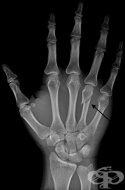

S62.3 Счупване на друга метакарпална кост

Заболявания

Счупванията на метакарпалните кости представляват 0.8% от всички счупвания на костите. Счупването на...

S62.4 Множествени счупвания на метакарпални кости

Най-често счупванията са в резултат на директна травма - при попадане на ръката между движещите се ч...